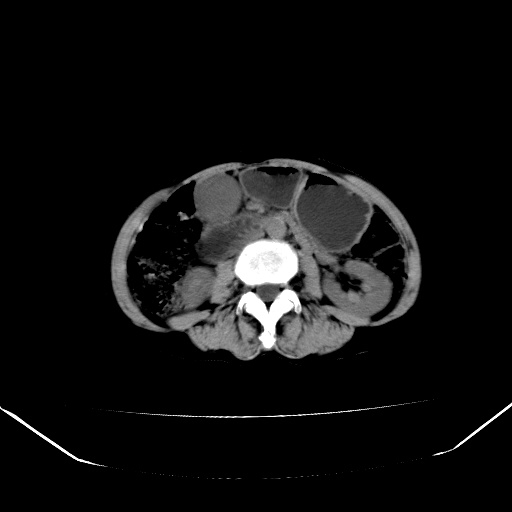

以下是引用jiangjing在2008-6-3 13:36:00的发言:[br]支持 胰头癌------肝内外胆管扩张,胰管扩张,胰头增大,增强见结节状轻度强化影,双管征明显

以下是引用卜一在2008-6-3 14:40:00的发言:[br]支持:胰头癌!(肝内外胆管扩张,胆囊高度扩张,胰管扩张,胰头增大,增强见结节状强化,明显低于胰腺强化密度,并明显见双管征)

以下是引用dyqct在2008-6-3 14:54:00的发言:[br]支持 胰头癌伴肝内外胆管扩张,胰管扩张,胰头增大,增强见结节状轻度强化影,双管征明显。肠系膜上静脉已受侵(已不能手术),建议离子植入治疗吧。